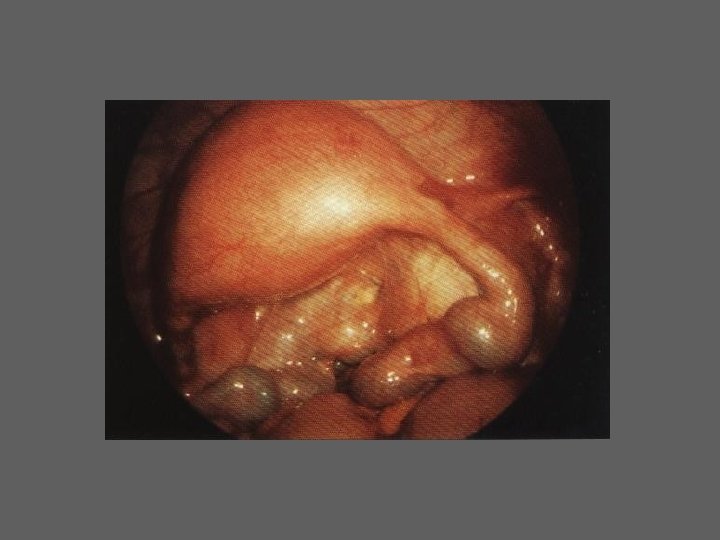

CELIOSCOPIA - INDICAÇÕES – Estudo e tratamento da infertilidade – Em todas as situações de sintomatologia obscura ou diversificada em que o exame ginecologico não revela uma patologia evidente: • Gravidez tubar • Doença inflamatória pélvica aguda • Algias pélvicas inespecíficas e crónicas – Realização de intervençõe cirurgicas

HISTEROSCOPIA - INDICAÇÕES Todas a situações em que se julgue vantajosa uma visualização completa da cavidade uterina, em particular: – Metrorragias – Dismenorreia adquirida – Infertilidade – Abortamentos de repetição e parto pré-termo – HSG anormal – DIU “perdido” – GIFT e ZIFT – Tratamento cirúrgico da patologia intracavitária: ● pólipos, miomas, septos, sinéquias, recessões endometriais ● baixos custos, reduzida morbilidade